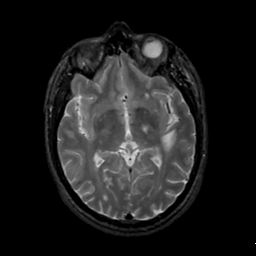

MR Study #1, February 10, 1991 -- Slice #24